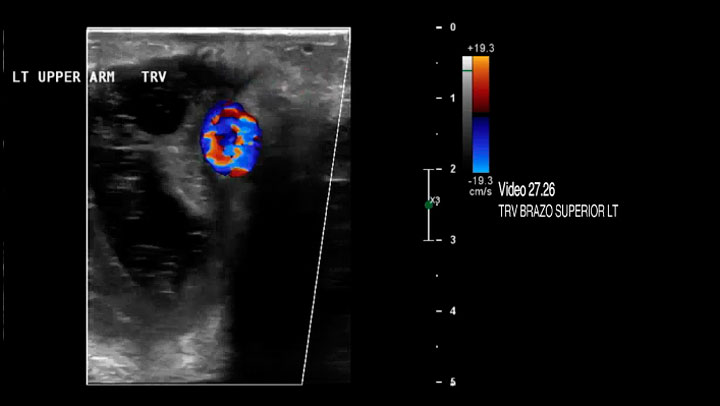

Video 27.26 Hematoma grande adyacente a fístula arteriovenosa (AVF)